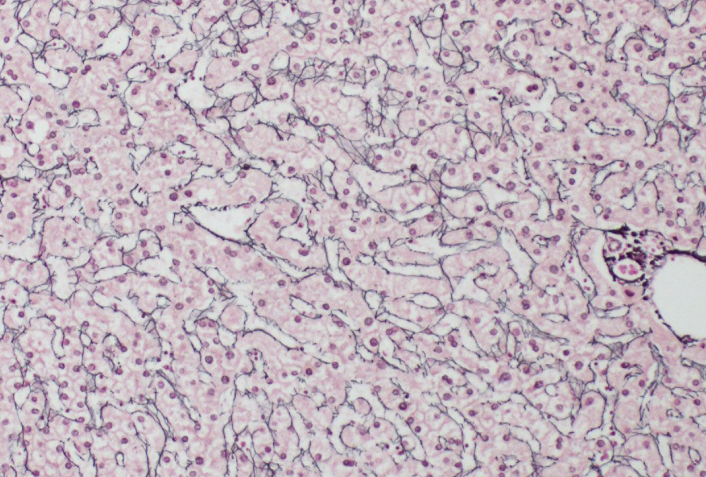

Special stain for reticulin fibers

Retic

Reticulin fibers provide supportive framework for the liver

True- framework for any highly cellular organ